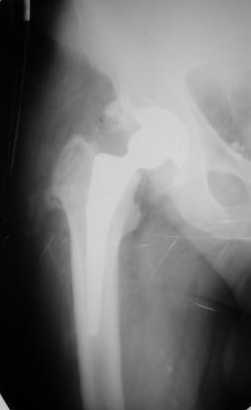

Больной Т. 56 лет, Диагноз: двухсторонний коксартроз 3-4 ст справа, 1-2 ст слева 2.10.08 выполнена операция тотальное бесцементное эндопротезирование. Использовался наружный доступ, положение на боку. Операция протекала без особенностей.

Выполнен послеоперационный ренгеноконтроль в прямой проекции. Рана зажила.

Уважаемый Глеб, предложенные снимки впечатлили! Никто не застрахован...